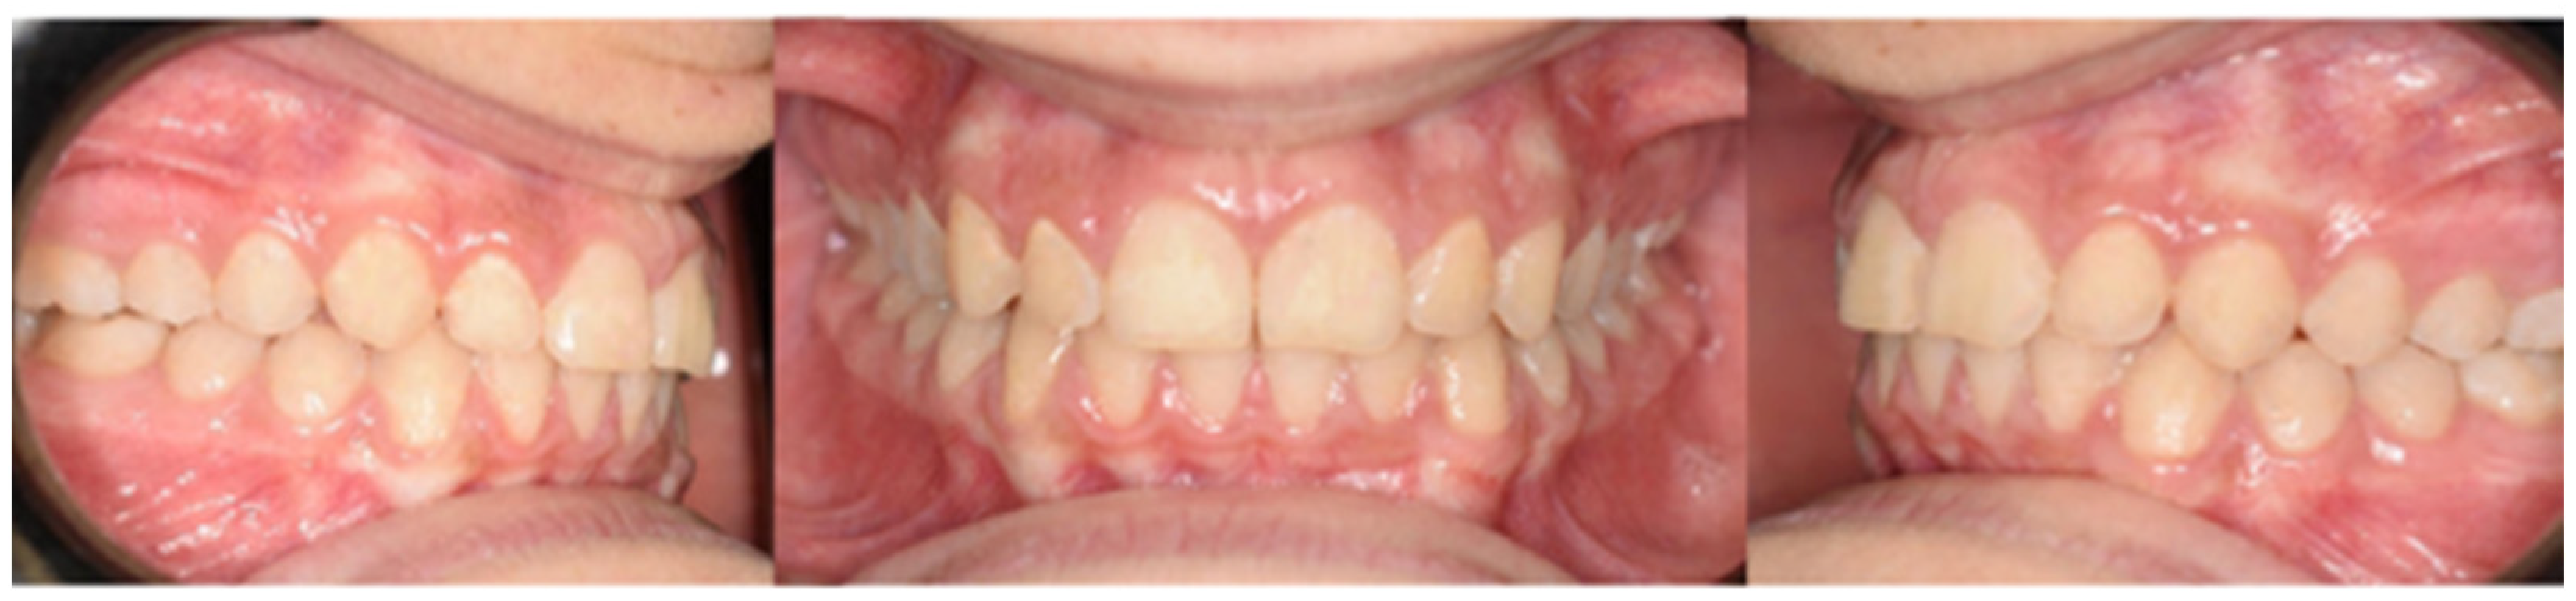

2. Presentation of Case Report

2.3. Treatment Progress

- Surgical exposure of the left mandibular canine using a diode laser (Doctor Smile, Lambda Spa, Brendola, Vi, Italy) for operculectomy and excision of fibromucous tissue. The corticotomy was performed using an ultrasonic piezosurgery system (Mectron Medical Technology, Carasco, Genova, Italy). A bottom (3M Unitek, Monrovia, CA, USA) was placed labially as close as possible to the canine’s coronal tip, combined with a metallic ligature and a cantilever (0.016 × 0.022 TMA, American Orthodontics, Sheboygan, WI, USA) without sutures (Figure 3a,b). The cantilever allowed for distal and buccal traction with light forces (1.7–2.8 ounces). A lingual arch was soldered (passive only on 31–32);

- Fixed multibrackets appliance (American Orthodontics Corp., Sheboygan, WI, USA, MBT prescription) were placed in the upper arch with 0.014 NiTi wire, bent back for controlling anchorage;

- After one month, a 0.016 NiTi wire was inserted in the upper arch;

- Fixed multibracket appliances were placed in the lower arch with a 0.014 NiTi wire, starting vertical traction of the canine. A bent back was used for controlling anchorage;

- After two months, the inferior left canine achieved a vertical position and reached its position in the arch. The bracket was replaced to adjust its axial inclination, and then a 0.016 NiTi wire was inserted;

- Before using stainless steel wire, a ligature from 16 to 26 and 36 to 46 for controlling anchorage was placed;

- 0.016 × 0.022 stainless steel wire was inserted in the upper and lower arches;

- 0.019 × 0.025 stainless steel wire was inserted in the upper and lower arches;

- Reverse Pin System” was placed on 13 and 23 to initiate class II biomechanics. Class II elastics (upper canines and first inferior molars) 3/8 4.5 ounces were used (Figure 3c). Class II elastics were used for 18 h every day;

- One year later, class I occlusion was achieved, and the class II elastics were used only during nighttime;

- Two years later, the appliance was deboned, and positioner retainers were given to the patient with the prescription to wear them every night.